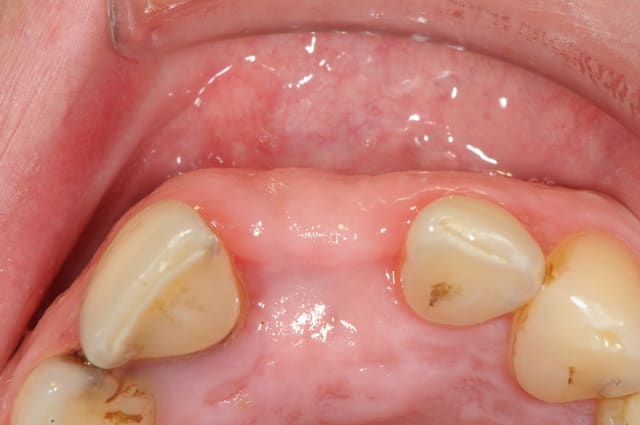

Dans le cas présenté, les images sont sur-exposées, couleur fade.

Avec un parodonte épais comme celui-ci, former la gencive n'est pas trop difficile.

Il y a aussi un gummy-smile et un sourire inversé, dommage après tant de couronnes.

The final result is a gummy smile with reverse smile line...too bad after all those crowns. A simple perio surgery could have give better result.